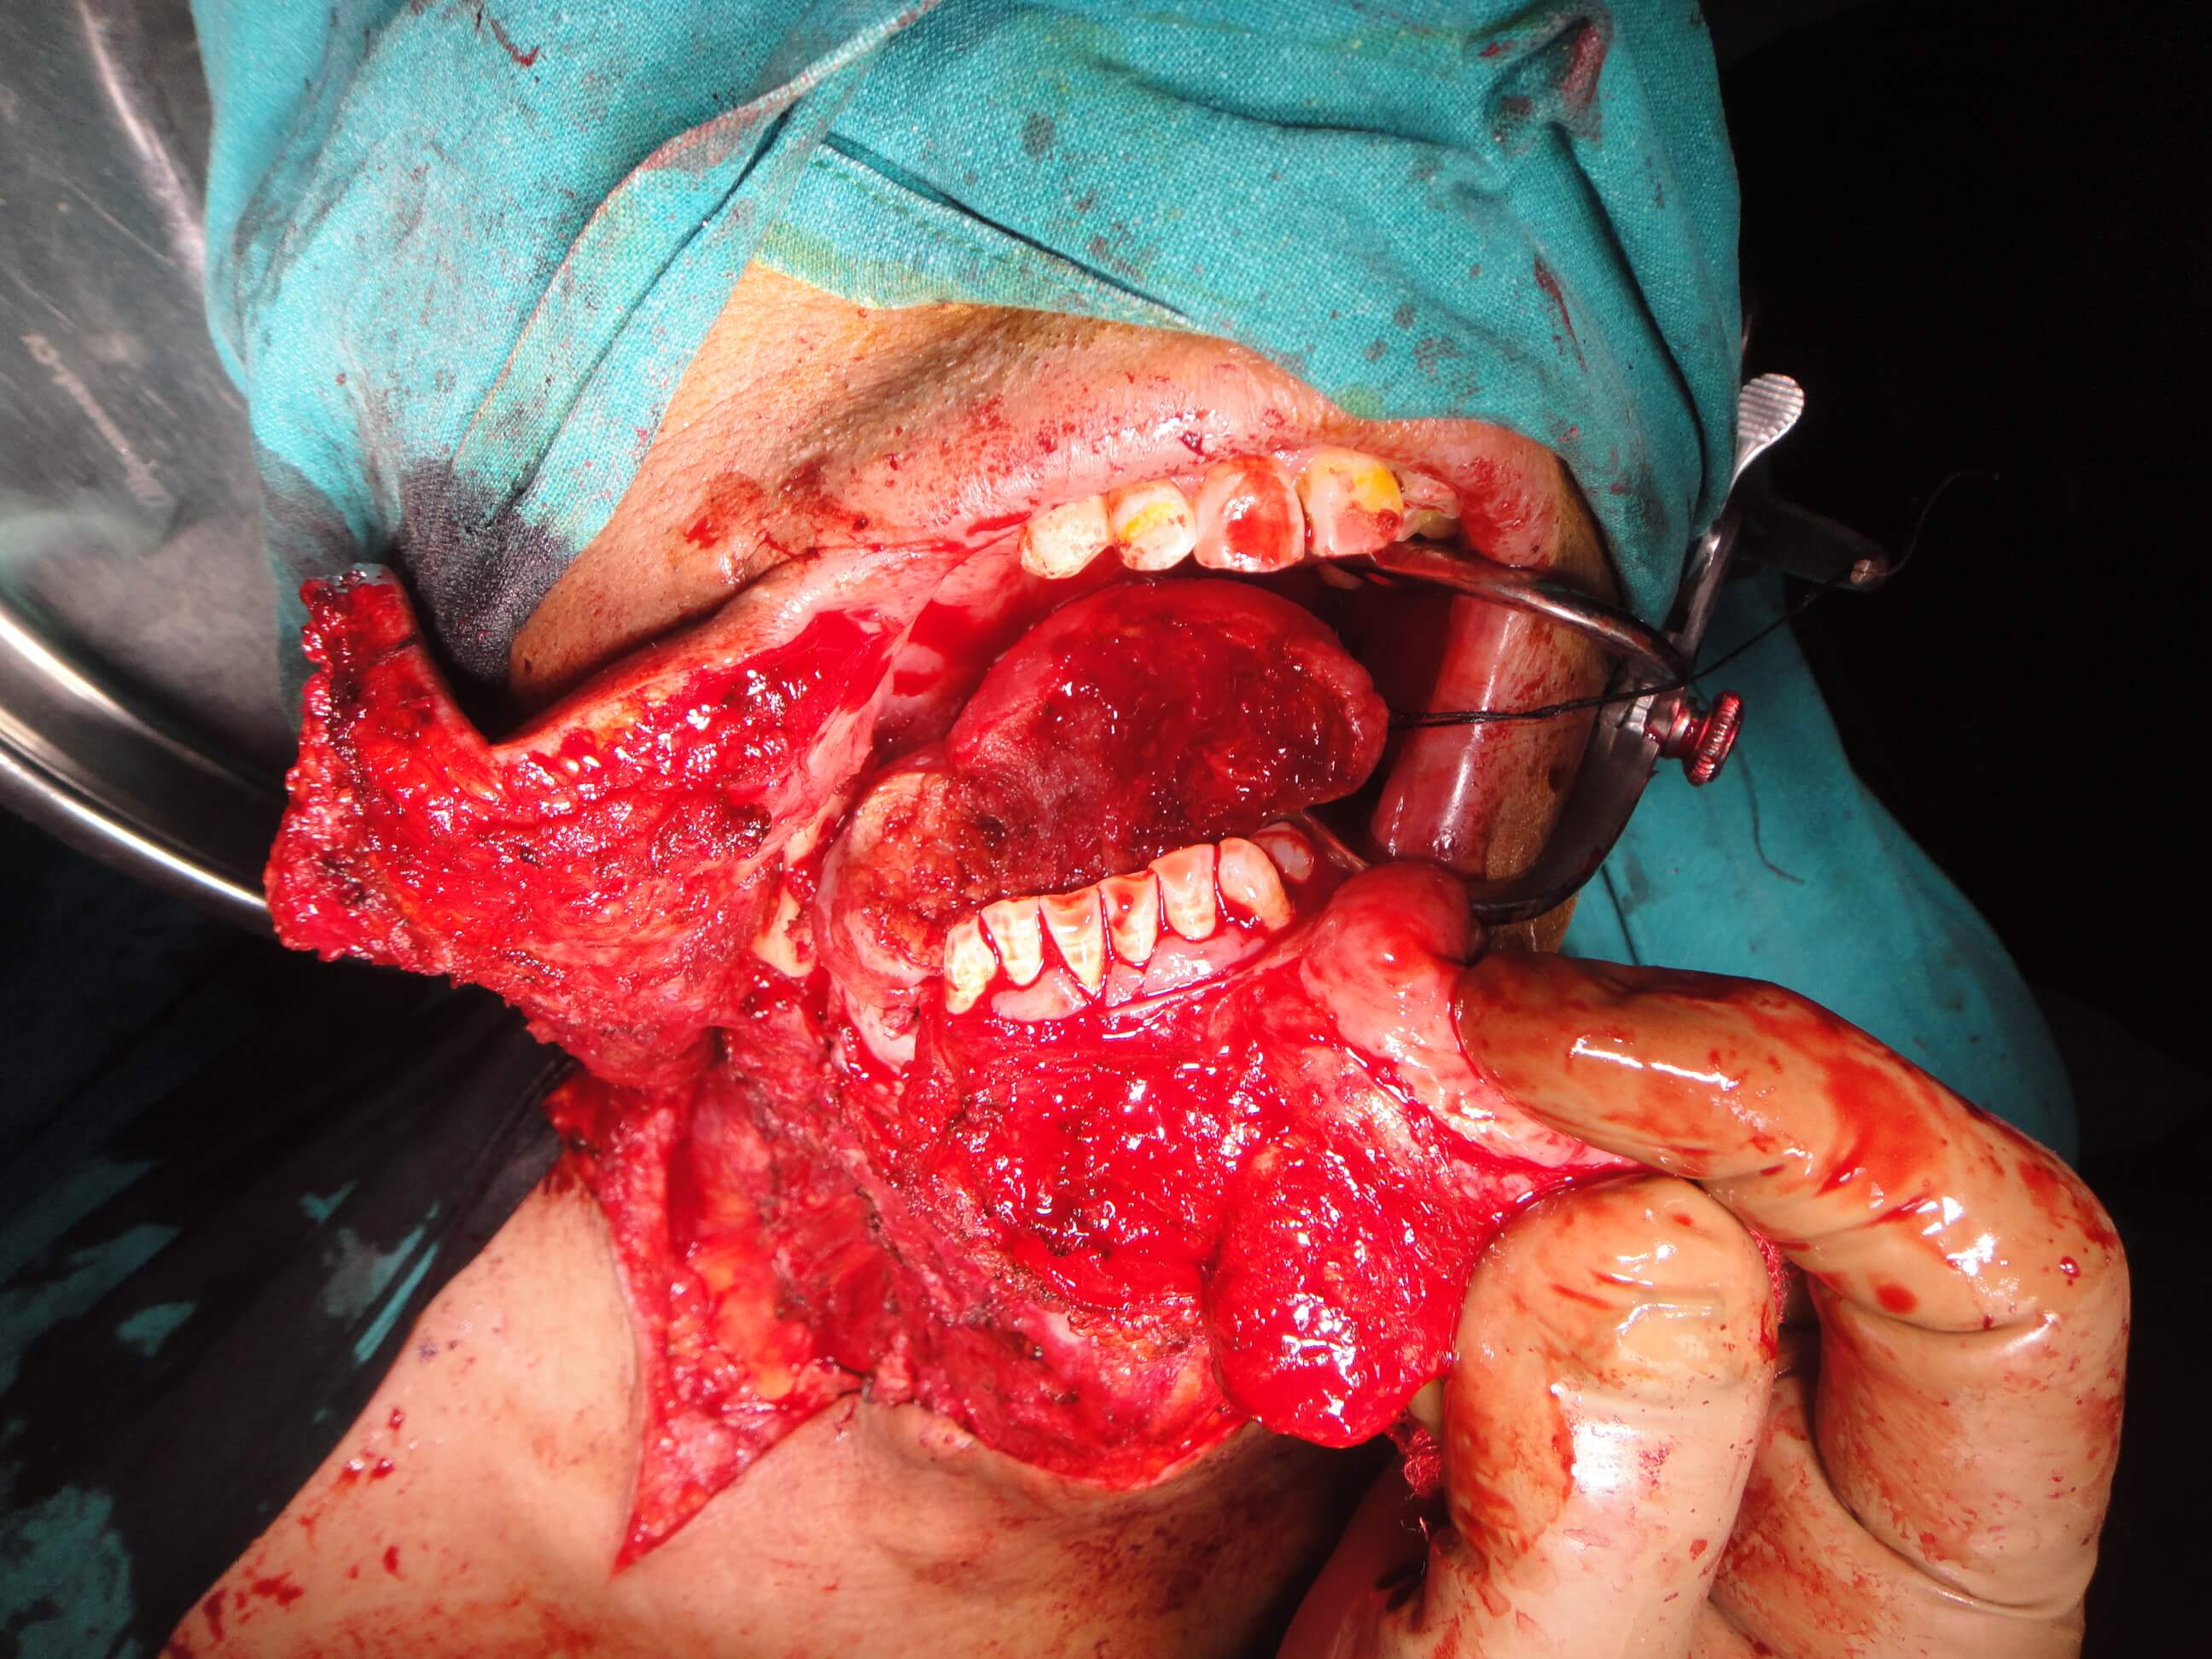

52 yrs old male suffering from right lower gingivo buccal carcinoma. Operated today for right radical neck dissection with right PM flap with right heminmandibulectomy.